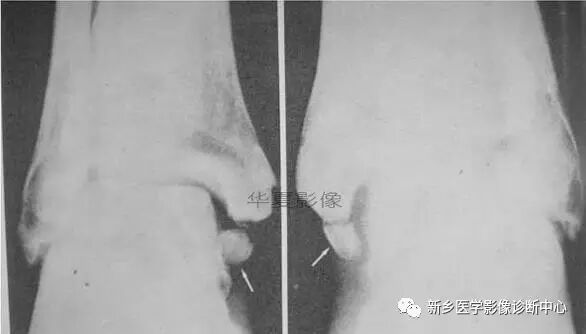

43、双侧内踝副骨化中心,胫下骨

• 双侧内踝副骨化中心,胫下骨。

• 双侧内踝副骨化中心。胫下骨之二,成年不愈合,常误诊为骨折。